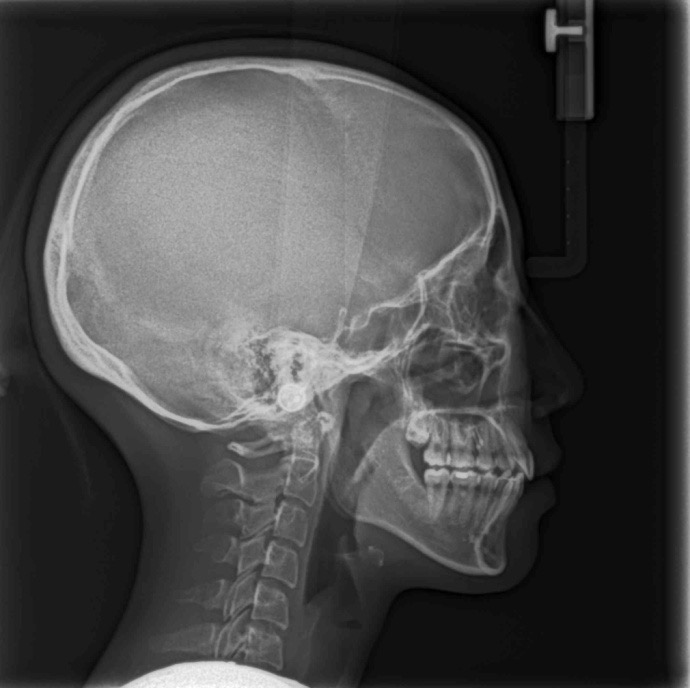

_PRE-TXNorm FMIA°47°55.0SNA°77.7°83.0SNB°70.2°80.0ANB°7.5°3.0FMA° 29.826PFH/AFH70.5°70Z Angle°50.3°77U1-FH113.0110.0IMPA°103.297.0U Lip to s’ line6.3 mm5.0L Lip to s’ line3.9 mm3.0OP-FH1215

头侧位片:

▲下颌后缩,骨性Ⅱ类

▲高角,颏部发育不足

▲上下前牙唇倾

Post-TXPRE-TXPost-TXNormFMIA°47°57.555.0SNA°77.7°76.883.0SNB°70.2°73.780.0ANB°7.5°3.13.0FMA° 29.828.026PFH/AFH70.5°65.970Z Angle°50.3°64.477U1-FH113.0103.7110.0 IMPA°103.291.197.0U Lip tos’ line6.3 mm3.25.0L Lip to s’ line3.9 mm1.03.0OP-FH1212.615